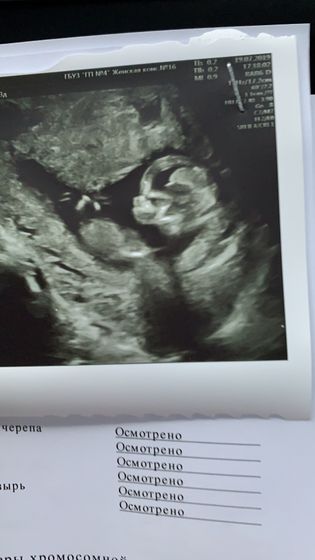

Сегодня была на узи. Кровь сдам завтра, так как узи было вечером.

Все у нас хорошо, отслойка прошла, плацента поднялась ( но ещё не так высоко как хотелось бы). Малыш без видимых патологий. Показали ручки, ножки, пальчики, красивые его глазки и сердечко. Предположили что сынок.

Вот беременна в пятый раз, а не могу привыкнуть к этому сказочному моменту своей жизни. Он уже красивый и умный малыш. Люблю его всем сердцем. ??

Ути пути… тьфу тьфу на Вас пусть растёт малыш. Такое фото чёткое!?

Мне кажется что у него даже лицо на фото какое-то серьёзное)))

Да, да. Мне тоже так показалось. Сосредоточенность такая?

Мама сказала что он просто занят был ?

Как будто у него на руках сидела бабочка, и он ее сдувает, и она летит ))))) моя ассоциация по фото ?

А я даже не заметила, и правда что-то есть